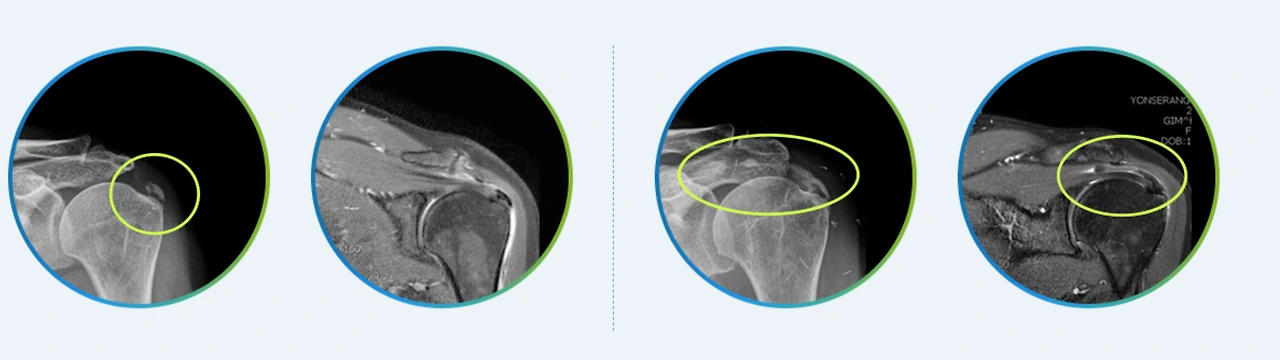

만일 초기지만 오랜 시간에 걸쳐 진행한 후에 발생하는 질환의 특징으로 통증이 심하거나 비수술적치료로도 개선이 되지 않는다면 관절내시경을 이용해 석회를 제거하는 수술을 할 수 있는데요. 통증의 원인을 빠르고 정확하게 제거하며, 최소절개로 인해 수술 후 회복시간이 짧은 장점이 있습니다.

어깨석회관절내시경.PNG